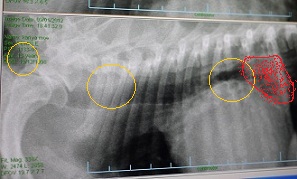

今日。レントゲンを撮ったのは、モエさんの続く”咳”に対して評価をするためです。

上の画像は、息を吐いた時のもの。

下の画像は、息を吸った時のもの。

モエさんは、息を吐いた時に黄色い○の部分(龍骨部)が潰れ、

気道が蛇行するそうです。

気管支虚脱って、黄色い○の3箇所のどこかで起こるらしくて

この日。たまたま 息を吐いた時に3箇所同時に細くなり、

気道が1本の細い線みたく潰れてしまってる

心臓疾患レベルは4/6。

このコの咳は、完全に気管支虚脱からくるものだそーです。

モエさんの咳は、心臓&気管支の影響。処方は変わらず・・とのことでした。

因みに赤い部分は肥大した左心室。

脊椎まで完全に食い込んだ状態。

こんな状態で、咳が出ない訳ないもんね・・(´Д`汗)